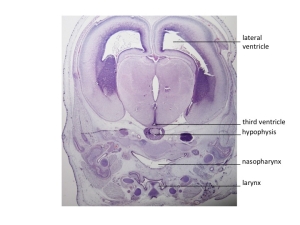

Stage 23

CfS 23

d41-44